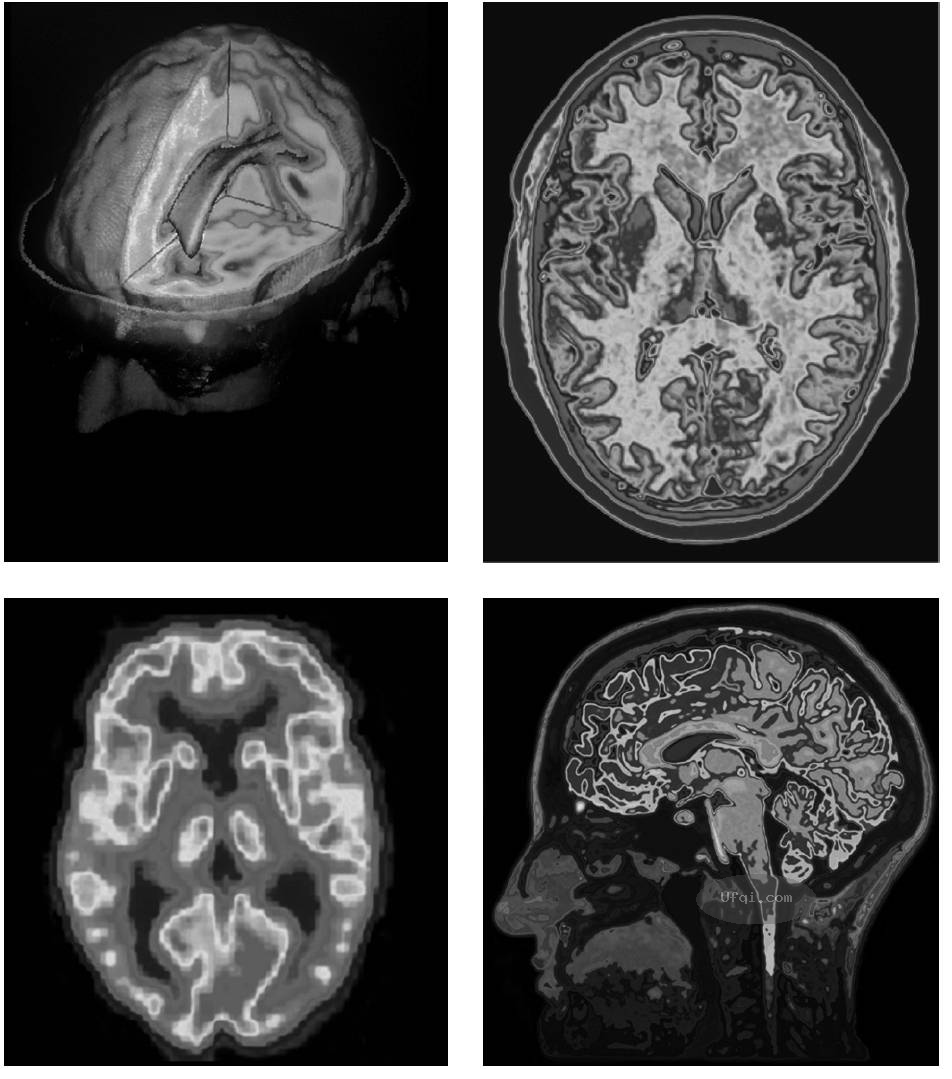

2.8.3 大脑皮层:人脑的思考帽

当你观察整个人脑的时候,你看到的大部分是凸起的大脑半球——它比你握紧贴在一起的两个拳头大一点。你可能会注意到它们被一条称为“胼胝体”(corpus callosum)的纤维束连接在一起,两个半球通过胼胝体进行沟通。近乎对称的两个半球包括厚厚的一层(被称为大脑,这部分的质量约为人脑的三分之二),以及大部分边缘系统。

大脑最外面薄薄的一层是大脑皮层(cerebral cortex),它是人脑的思考帽:它独特的褶皱表面使得超过100亿的神经元可以聚集在几毫米的厚度中。如果把褶皱摊平,皮层表面大约有一张打开的报纸那么大。但是由于其表面卷曲盘绕,我们只能看到大约三分之一的皮层。

一个健康的人脑分成两半,这样就露出了脑表面的回(凸起)和沟(凹陷)。这些沟回形成的褶皱可以使数十亿的脑细胞挤进很小的一个区域。

大脑皮层有什么功能呢?它就是内在的你!它是我们最强大的心理力量所在的地方,它加工我们所有的感觉,存储记忆,并且做出决策。它还有很多其他功能,我们在后续小节中讨论大脑各个脑区时会介绍这些功能。